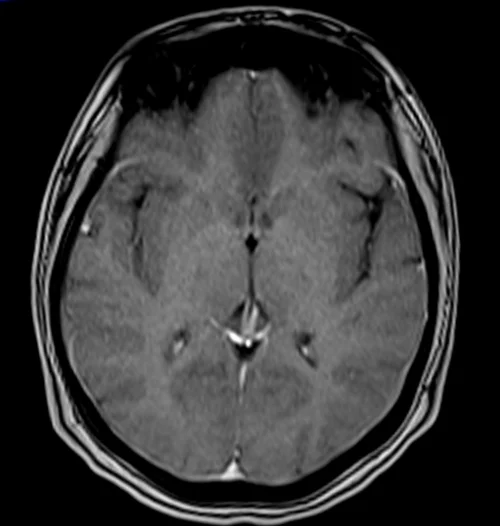

MRI VIBE(LAVA-XV/THRIVE/TIGRE) Post Contrast

The easiest way to identify T1 VIBE post-gadolinium images is to look for blood vessels in the body (e.g., arteries and veins in the brain, neck, chest, abdomen, upper limbs, and lower limbs). Blood vessels and pathologies with high vascularity appear bright in T1 VIBE post-gadolinium images. All the other characteristics of the T1 VIBE post-gadolinium images remain the same as the T1 VIBE images.

Moving blood : – bright

White matter : – whiter

Gray matter : – gray

Pathologies with hypervascularization will appear bright on T1 VIBE post-contrast gadolinium images. Examples of such pathologies include tumors like hemangioma, lymphangioma, hemangioendothelioma, Kaposi’s sarcoma, angiosarcoma, hemangioblastoma, as well as inflammatory processes like discitis, meningitis, synovitis, arthritis, and osteomyelitis. Pathological processes with no vascularity will remain unenhanced, appearing dark on T1 VIBE post-contrast gadolinium images.

VIBE AXIAL POST CONTRAST SEQUENCE USED IN UNCOOPERATIVE PATIENTS BRAIN IMAGING